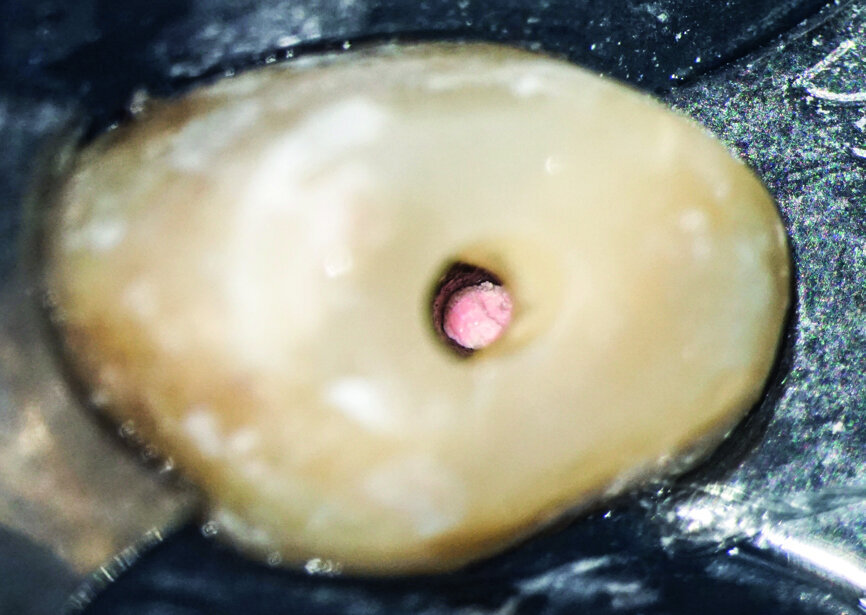

After isolation of the tooth (Fig. 3), an access cavity was created using high-speed diamond burs and ultrasonic tips (Figs. 4–8). Pre-flaring in the coronal and middle thirds was done with the HyFlex EDM 25 instrument (at a torque of 4 Ncm and a speed of 500 rpm). It is a proven fact that pre-flaring allows an increase in the instrument size that binds in the root canal, irrespective of the discrepancy between the size of the file and anatomical diameter. [19–21] Afterwards, canal scouting was performed using an ISO size 10 stainless-steel K-file up to working length. Upon establishing the working length, with the help of an apex locator, the 10/05 EDM file (glide path file) was used up to working length (at a torque of 3 Ncm and a speed of 300 rpm). Subsequently before finishing the preparation with the 25 EDM file, the 20/05 EDM (preparation file) was used to full working length (at a torque of 3 Ncm and a speed of 400 rpm). At this point, the working length was confirmed again with an ISO size 20 NiTi K-file. Root canal shaping was completed with the 25 EDM file, which was inserted to full working length (at a torque of 3 Ncm and a speed of 400 rpm; Figs. 9–12).